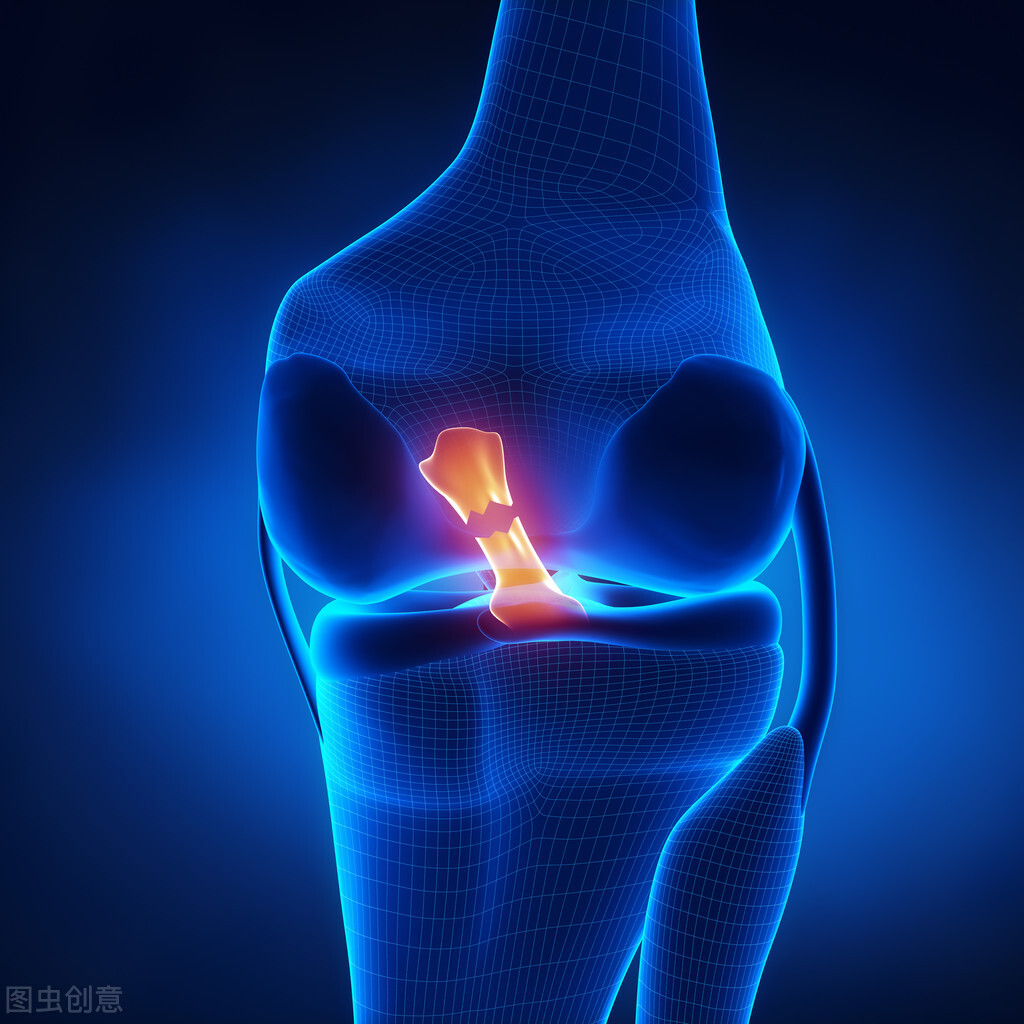

前交叉韧带是膝关节对抗向前移位的主要稳定装置。前交叉韧带撕裂是由膝关节的扭转或过伸*力暴**超过其强度所致。虽然可以出现部分撕裂,但是前叉韧带完全撕裂更常见。大部分前叉韧带撕裂为非接触性损伤。前交叉韧带损伤常伴严重的半月板撕裂、内侧副韧带的撕裂,少数情况下也会出现外侧韧带复合体或后交叉韧带的损伤。膝关节损伤造成的多发韧带损伤比较罕见,它们会导致严重的膝关节不稳,并且可以伴有腘动脉损伤;这是危及肢体的紧急情况。

前交叉韧带重建术